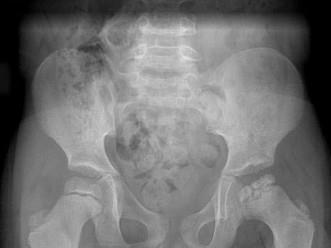

问题 男,6岁,髋痛、跛行,请结合CR检查,选出最可能的诊断 ( )

选项 A、骨囊肿 B、软骨肉瘤 C、股骨头骨骺缺血坏死 D、骨肉瘤 E、髋关节结核

答案 C